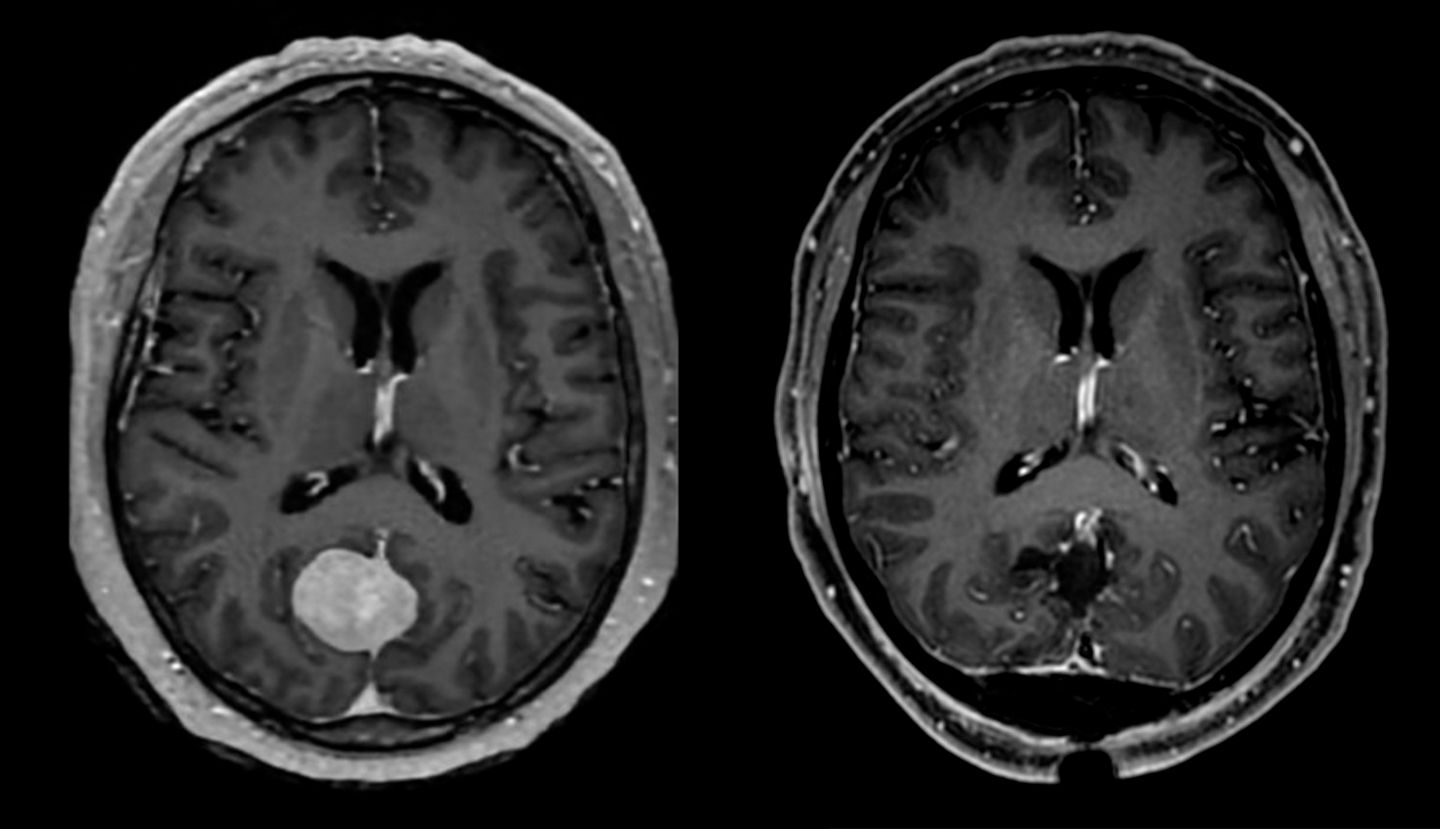

Metastase vor Operation (links) und nach Entfernung (rechts).